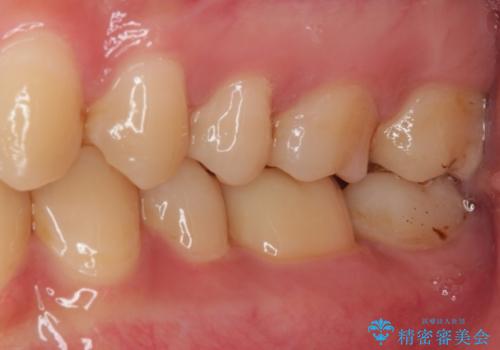

オールセラミッククラウンとしたことで見た目の改善やものが挟まる不快感の改善だけでなく、舌触りも良くなりました。